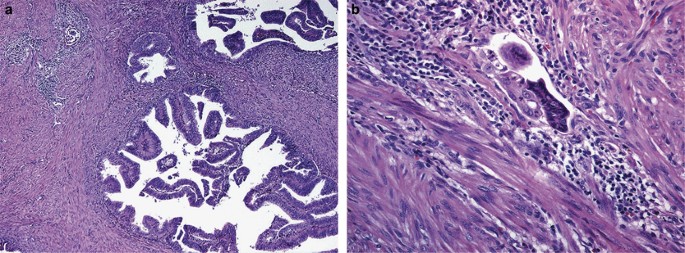

ECa with a villoglandular pattern

This tumor is characterized by long, slender, finger-like papillae, containing a fibrovascular core and lined by columnar cells with no or mild cytologic atypia. The nuclei are vertically oriented in relation to the basement membrane and the surface of the papillary structures is smooth4 (Figure 3a and b). Its incidence has been reported to range from 13% to 31%.4, 5 Most examples of this variant occur intermixed with a typical ECa (60%), whereas it occurs in its pure form in 40%.5 Some investigators have found that the presence of a villoglandular pattern within the myoinvasive component of an ECa is associated with a higher frequency of vascular/lymphatic invasion and lymph node metastasis, as well as a worse outcome when compared with myoinvasive ECa, usual type 1.4 (Figure 4a and b). A similar experience has been found in our practice; however, the validity of these observations could not be confirmed in a large Gynecologic Oncology Group study.5 This discrepancy could be related to differences in the methodology used in these two studies.6